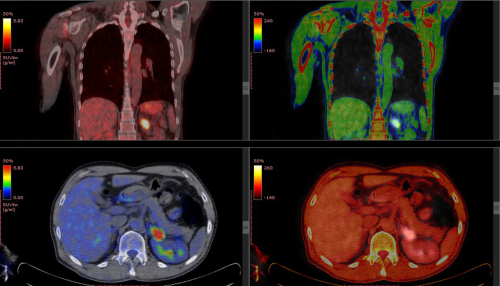

Diagnostic nuclear medicine involves the use of radioactive tracers to image and/or measure the global or regional function of an organ. The radioactive tracer (radiopharmaceutical) is given to the patient by intravenous injection, orally or by other routes depending on the organ and the function to be studied. The uptake, turnover and/or excretion of the tracer substance is then studied with a gamma camera, positron emission tomography (PET) camera or another instrument, such as a simple stationary radiation detector. The uptake of the tracer is generally a measure of the organ function or metabolism or the organ blood flow. ©IAEA